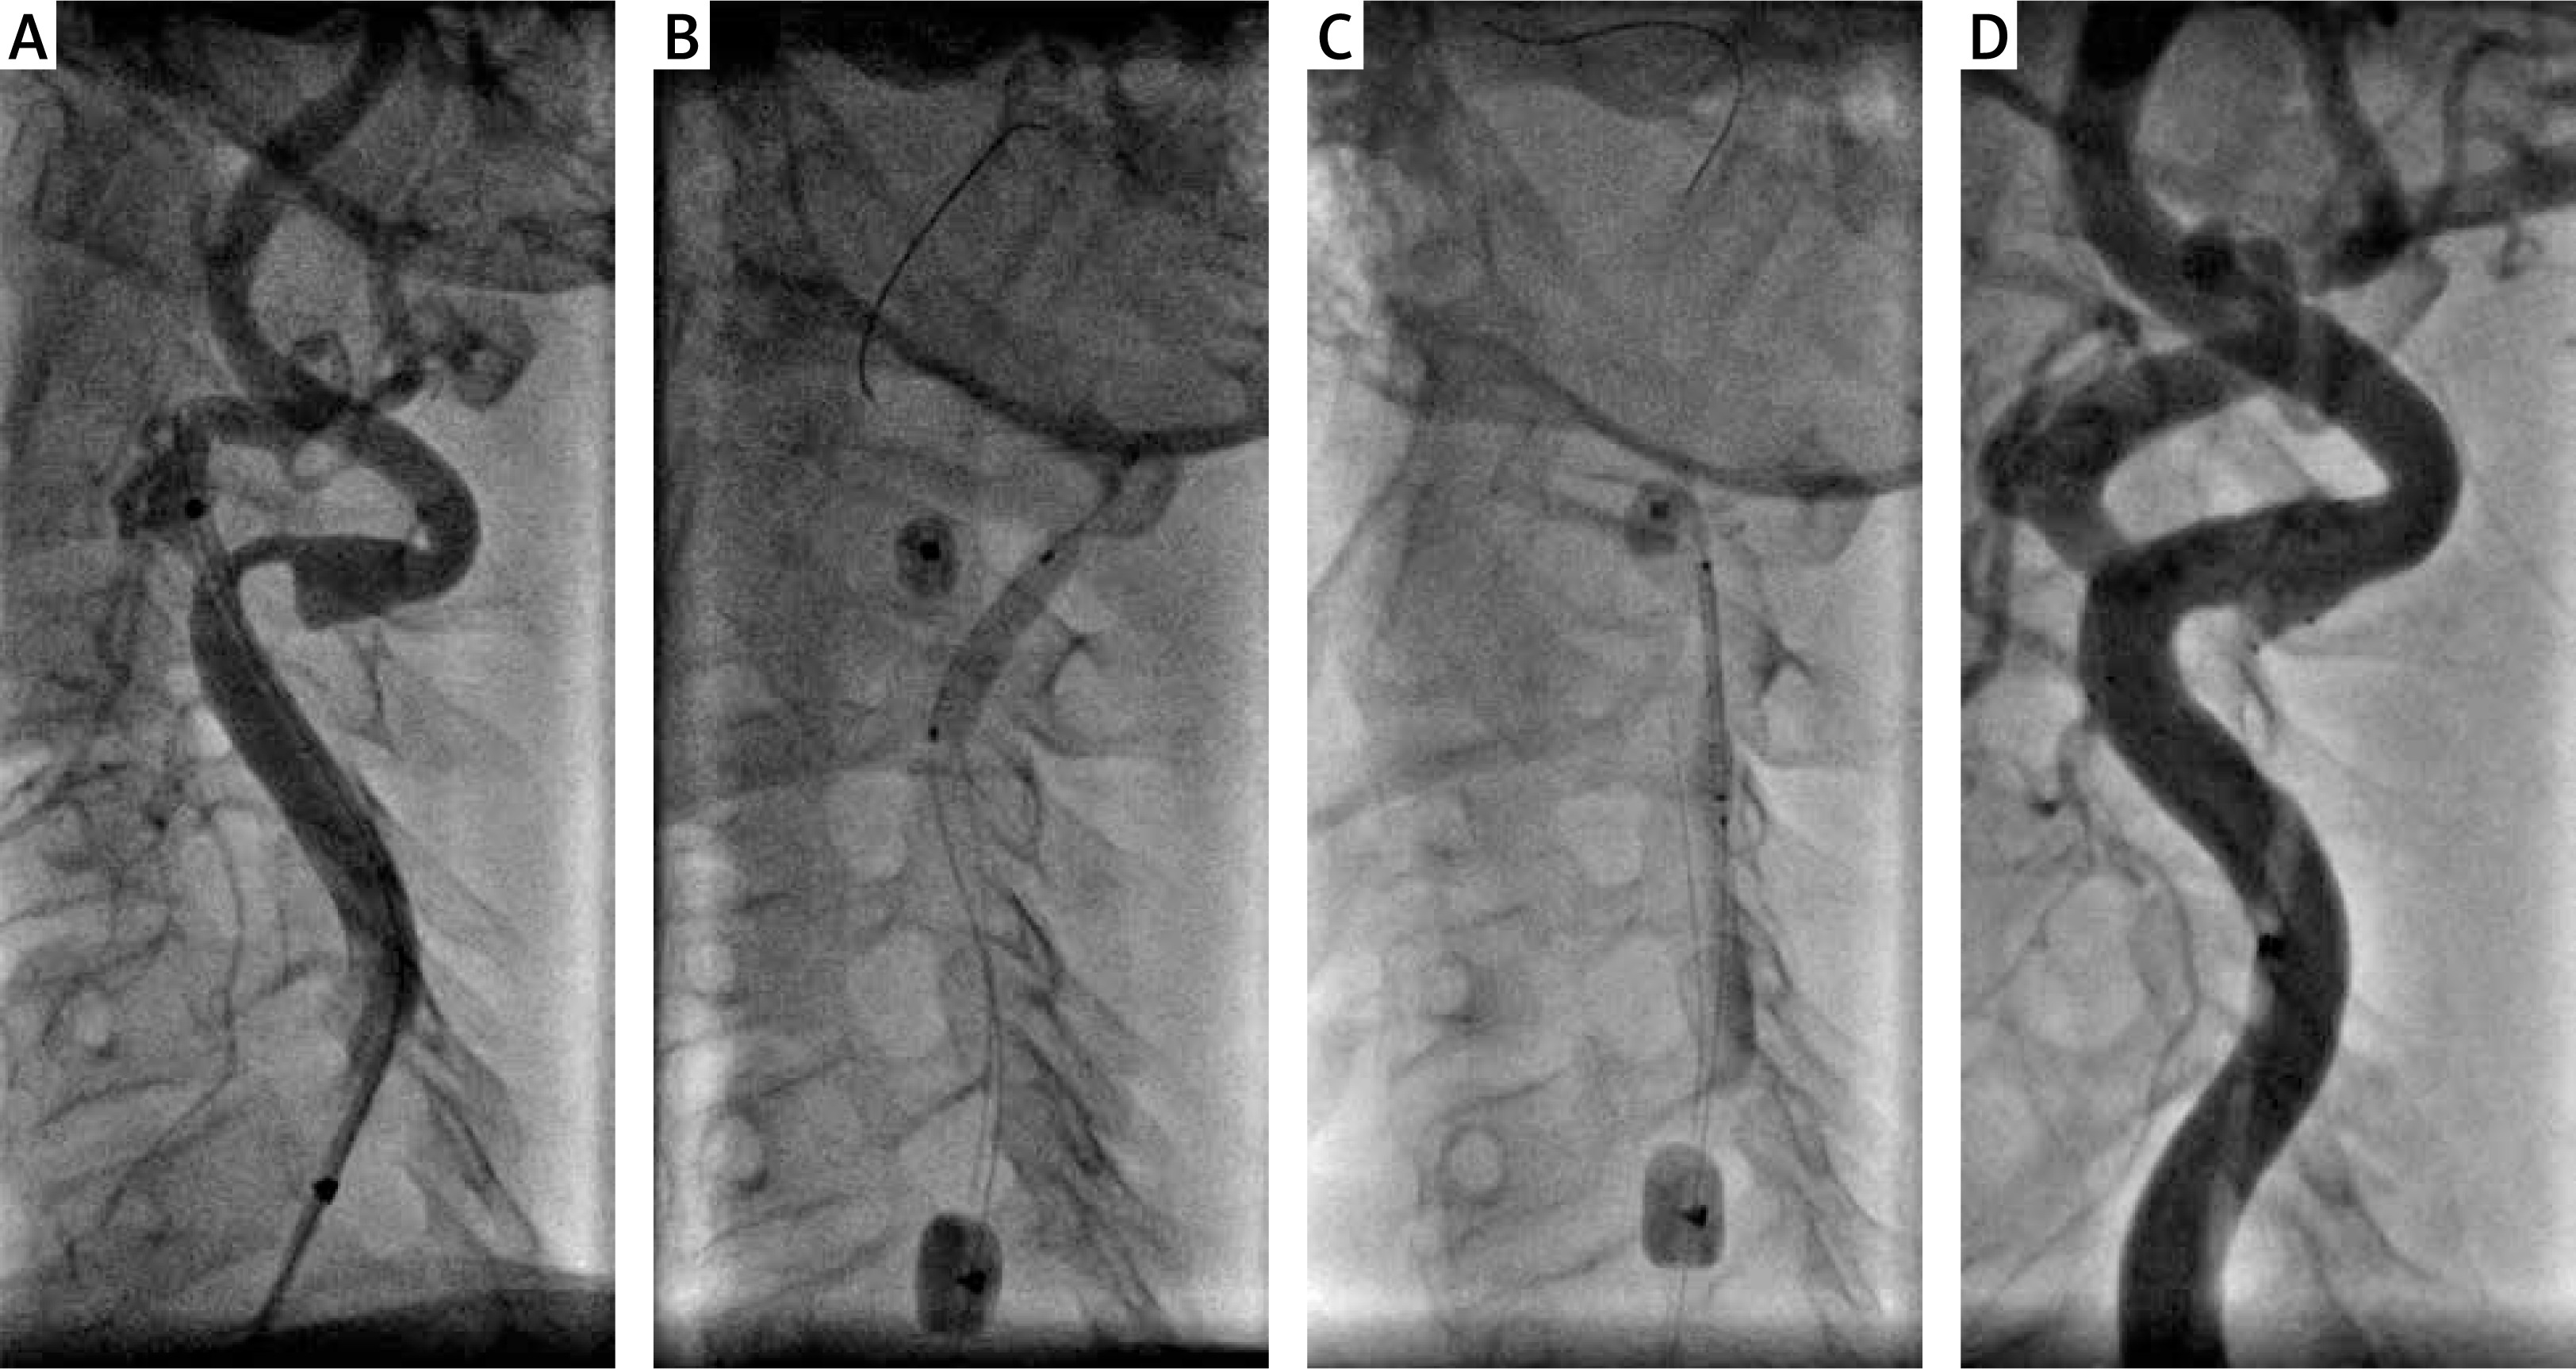

Figure 3

A – Tight symptomatic left internal carotid artery stenosis with severe double angulation > 90°. The use of an 0.014 inch Grandslam support guidewire required due to the extreme angulation of the artery. B – Proximal protection with 8 Fr Mo.Ma – predilatation with 3.0 × 20 mm coronary balloon catheter. C – MER™ stent 7.0 × 20 mm implantation. D – Final optimal angiographic result